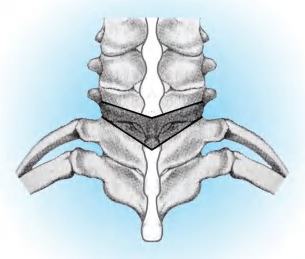

(2)用C形臂X线机确定置钉位置,在C 4 、C 5 、C 6 两侧的侧块上置入侧块螺钉。再在T 2 、T 3 两侧的椎弓根内置入椎弓根螺钉(图2-58)。

(3)然后在C 7 ~T 1 椎板间隙上做V形截骨(图2-59)。截骨间隙的宽度为上一椎弓根的下缘至下一椎弓根的上缘,一般为8~12mm,揭开椎板盖暴露硬脊膜及两侧的脊神经根(图2-60),向椎间孔外游离脊神经根,将伴随的血管束电烙止血。将脊神经根向上或向下牵开,暴露椎体后缘和椎间隙(图2-61),沿着椎间盘的外侧向前剥离、暴露椎体及椎间盘的外侧面,插入撬板暴露椎体和椎间盘的前外侧,用撬板隔开椎前软组织、节段血管及胸膜。

图2-58 截骨前颈椎置入侧块螺钉,胸椎置入椎弓根螺钉

(2)侧块螺钉和椎弓根螺钉的进钉方向,如图2-69、图2-70所示。

A.在轴像上向外侧倾斜25°;B.侧块螺钉置入后的位置

图2-69 侧块螺钉的进钉方向

A.进钉点位于上关节面的下外方,相当于横突根部直径的中点;B.在轴像上向内倾斜30°~40°;C.在侧位像上与椎体上缘平行进钉

图2-70 上胸椎椎弓根螺钉的进钉方向